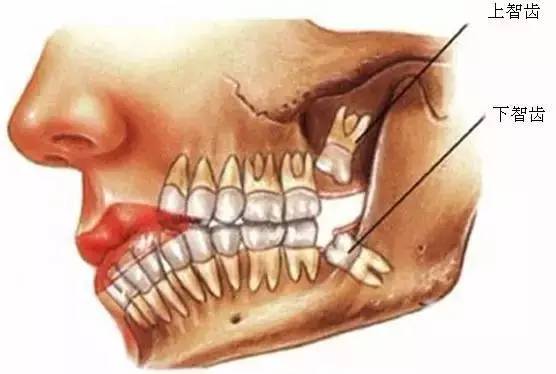

口腔醫(yī)院牙醫(yī)表示,智齒這個磨人的小妖精,簡單的說就是人類演化過程的棄兒。觀察古人類和其他靈長類的頜骨,會很容易發(fā)現(xiàn),他們的頜骨與現(xiàn)代人相比更大,頰舌面寬度更寬,近遠中向長度更長。頜骨空間充足,智齒的生長方向和咬合關(guān)系一般都比較正常,很少出現(xiàn)現(xiàn)代人智齒阻生的情況,說明頜骨提供的空間跟智齒的萌出狀態(tài)有直接的關(guān)系。

640 (20).jpg

所以,簡單的說智齒實際上是人類演化過程中被放棄的生物學性狀,由于個體遺傳基因的不同,在這個性狀的表達上存在差異,是否萌出智齒以及萌出數(shù)量都因人而異,有人是4顆全部萌出,有人只萌出1顆,也有人1顆智齒也不長的。